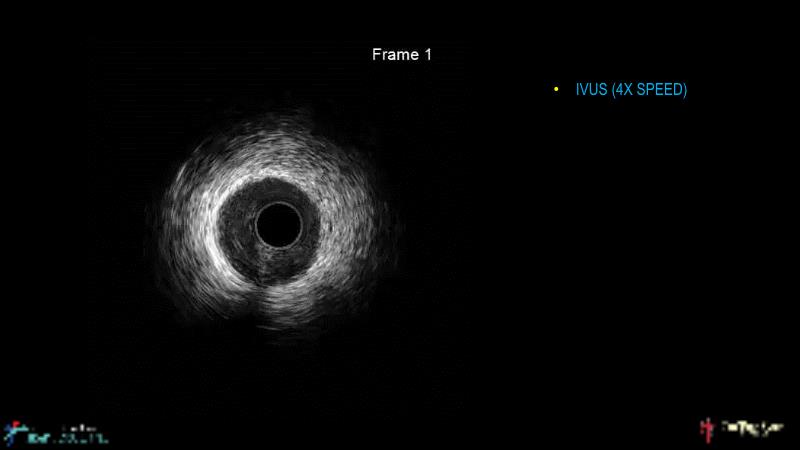

A hybrid approach in complex PCI: can DES and DCB be complementary?

Watch this case-based session to follow discussion about how to choose between DES & DCB, how both can be complementary in diffuse disease as well as in complex PCI, and how physiology and imaging can help guiding PCI, and follow a patient's treatment live.

- To learn the tips and tricks in performing complex PCI intervention with DES and/or DCB